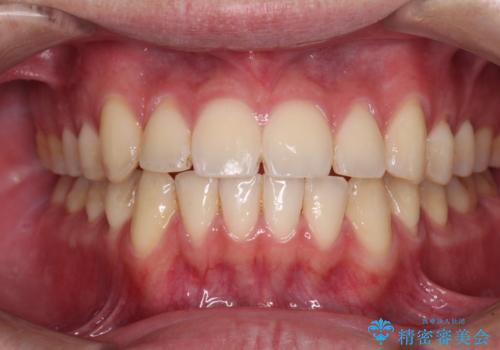

矯正歯科治療 → 叢生(でこぼこ・八重歯)

気になる八重歯を目立たない装置で改善 ハーフリンガル矯正